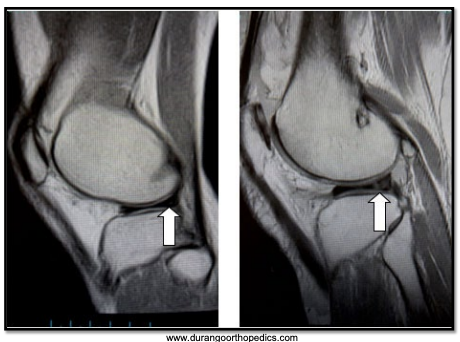

A

Left: Torn meniscus

Right: Normal meniscus

MRI has taken over for knee arthogram